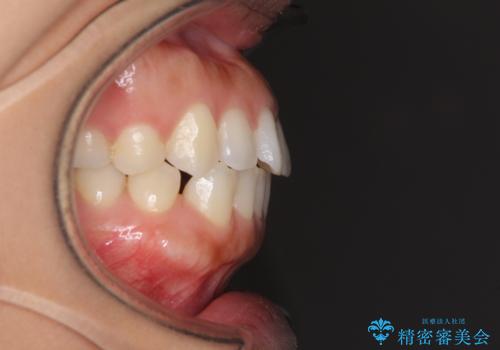

受け口傾向の前歯 すきっ歯の改善

- 前歯の隙間と口元の突出感を気にして来院された患者様です。

嚥下時に舌を突出させる癖があり、成長期に下顎が有意に成長し、歯と歯の間に隙間ができてしまいました。

舌の癖を改善し、インビザラインにて治療を行うこととしました。

舌癖を改善したことで、隙間や突出感を改善することができました。

隙間は後戻りしやすいため、舌側を細いワイヤーで固定することとしました。